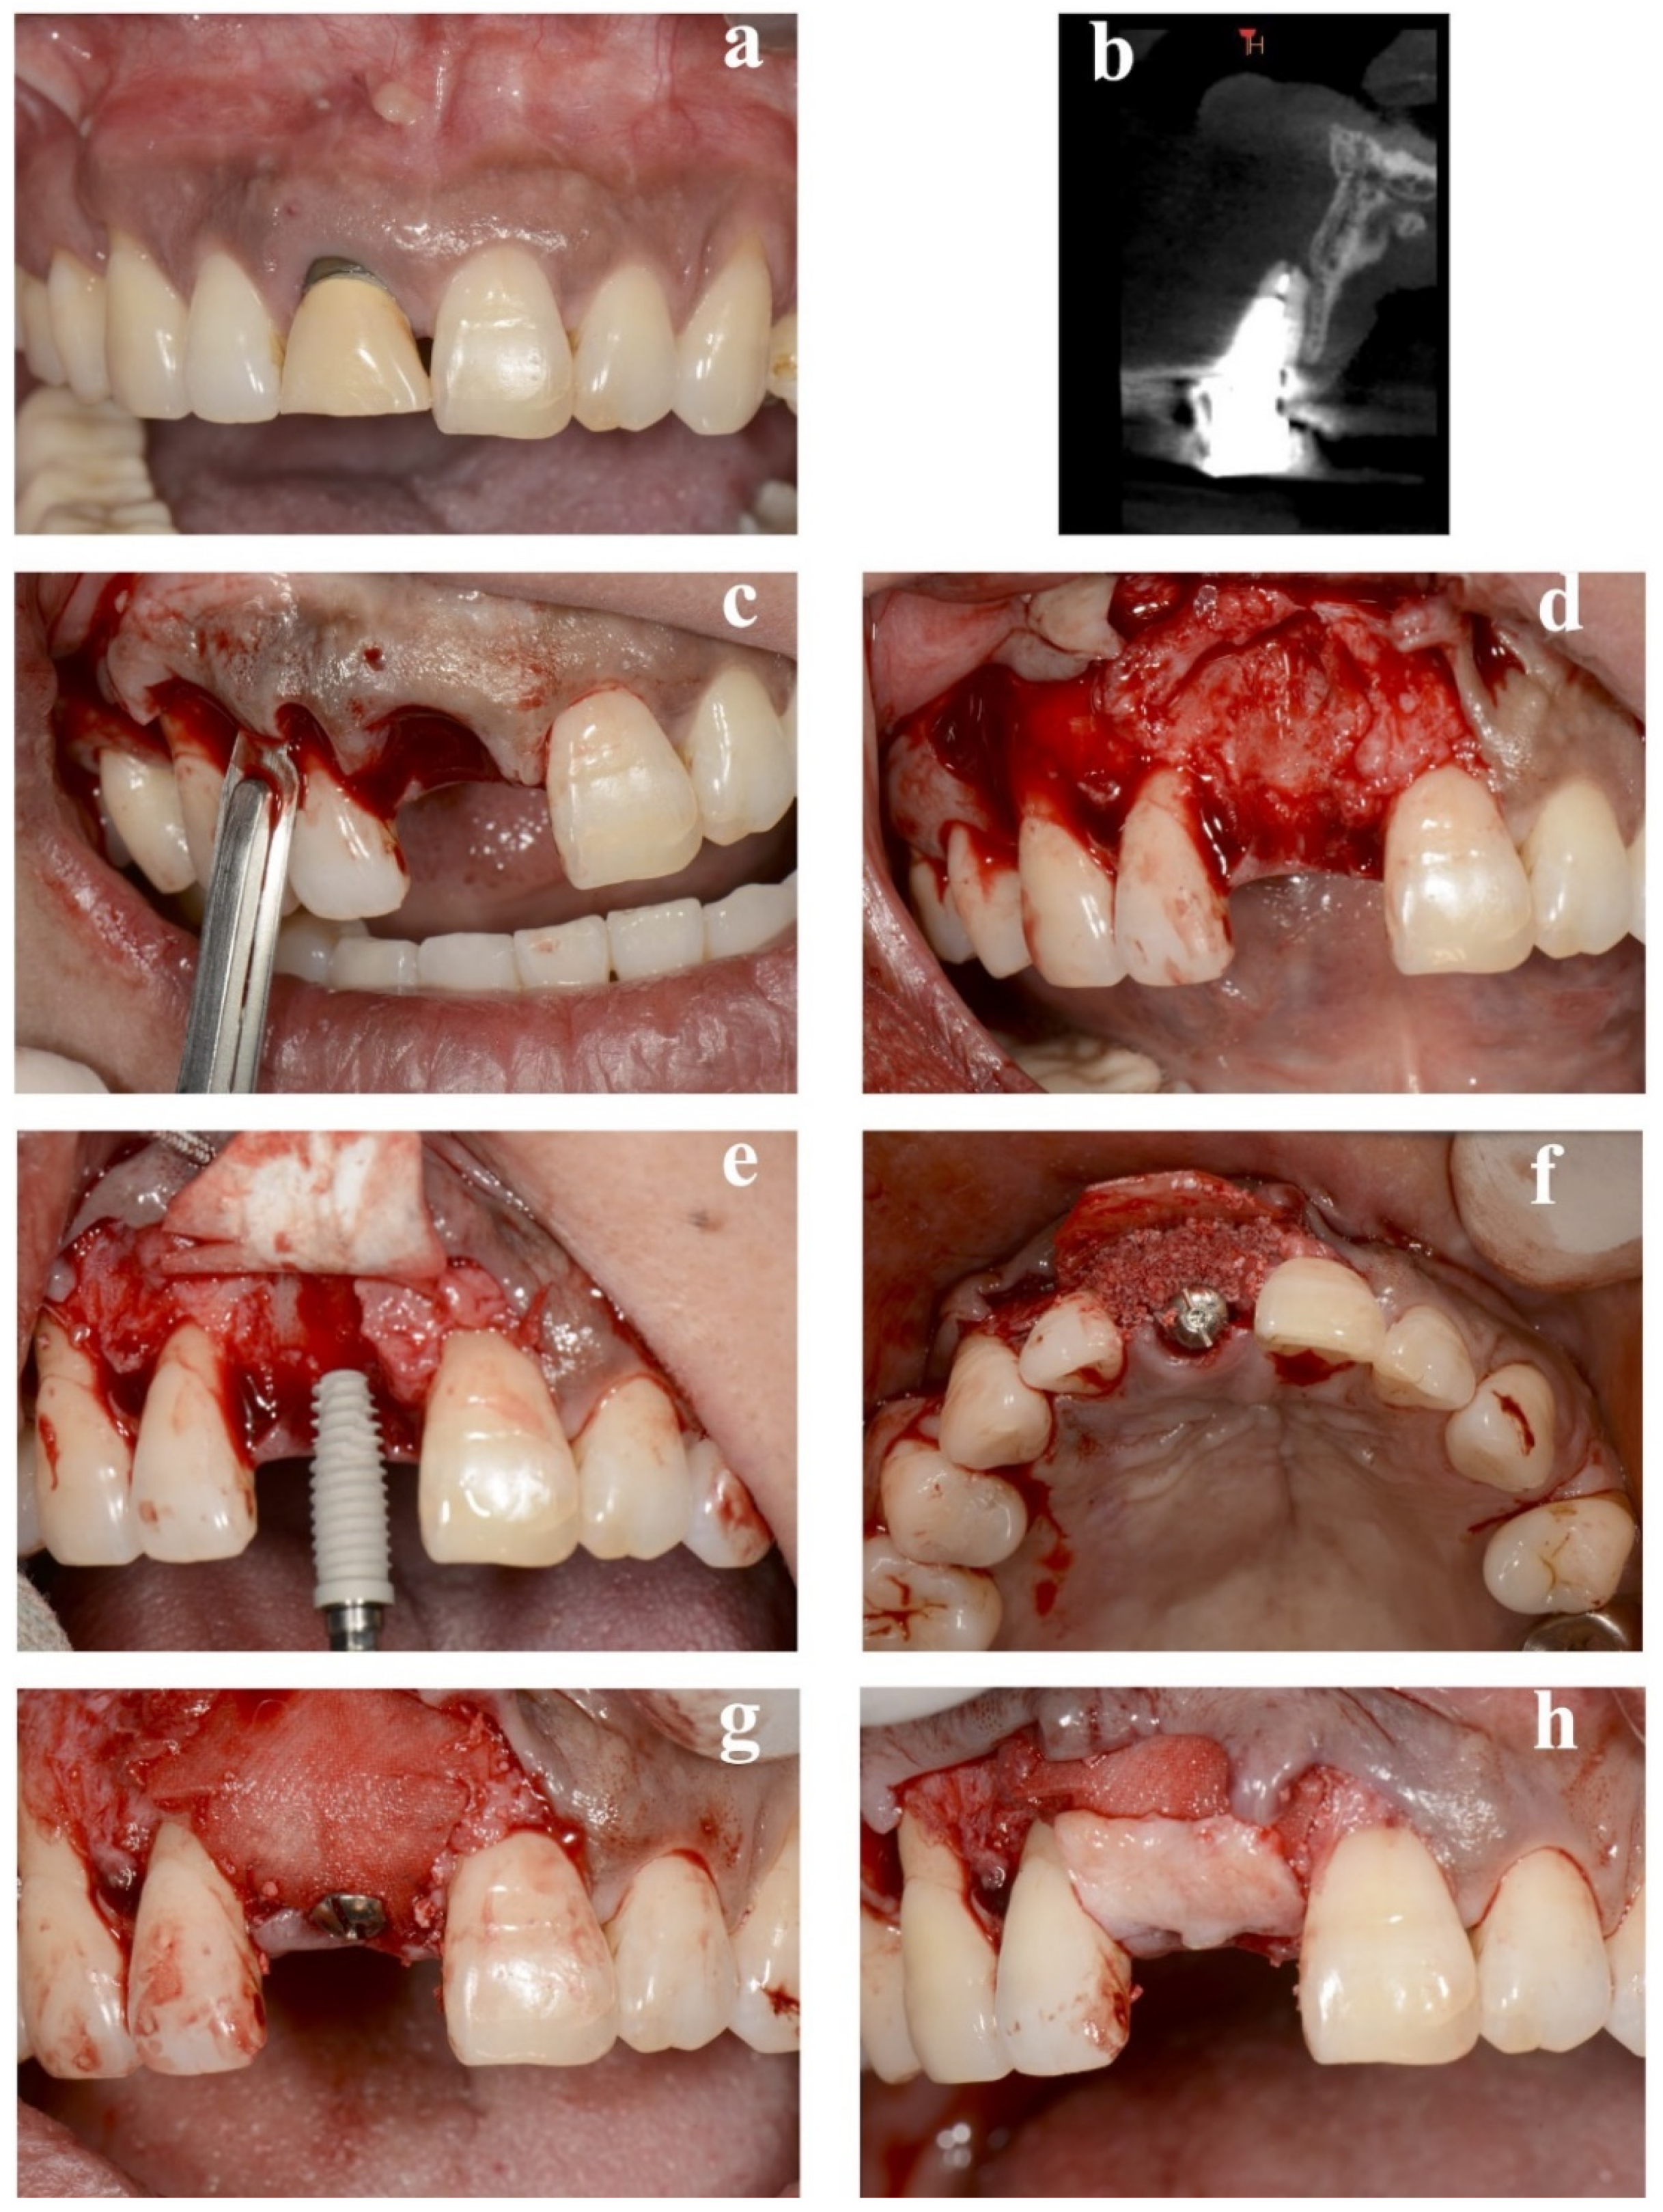

Eleven patients (eight women and three men, with a mean age of 45.5 ± 9.5 years) received single dental implant placements. The details of all cases are provided in Table 1. No implants exhibited any adverse or unanticipated events. Preoperative and perioperative photographs of representative immediate case #2 are presented in Figure 2. The average duration of nonloading was 19.7 ± 4.1 weeks.

Figure 2. Replacement of a maxillary central incisor with an immediate implant in case #2. (a) Presurgical frontal view. (b) Cross-sectional view of preoperative CBCT. (c) Representation of the intracrevicular partial-thickness incision made around the natural teeth. (d) Preparation of periosteum tabs just apical to the buccal dehiscence in the lengths of 2–3 mm. (e) Insertion of a resorbable membrane beneath the periosteum tab. Execution of implant placement following the preparation of a pouch for lateral GBR. (f) Treatment of the internal space of the pouch surrounded by the resorbable membrane and exposed labial implant surface with a demineralized bovine bone mineral. (g) Covering of the surgical site with the membrane. (h) Securing of the connective-tissue graft to the periosteum. CBCT: cone-beam computed tomography, GBR: guided bone regeneration.